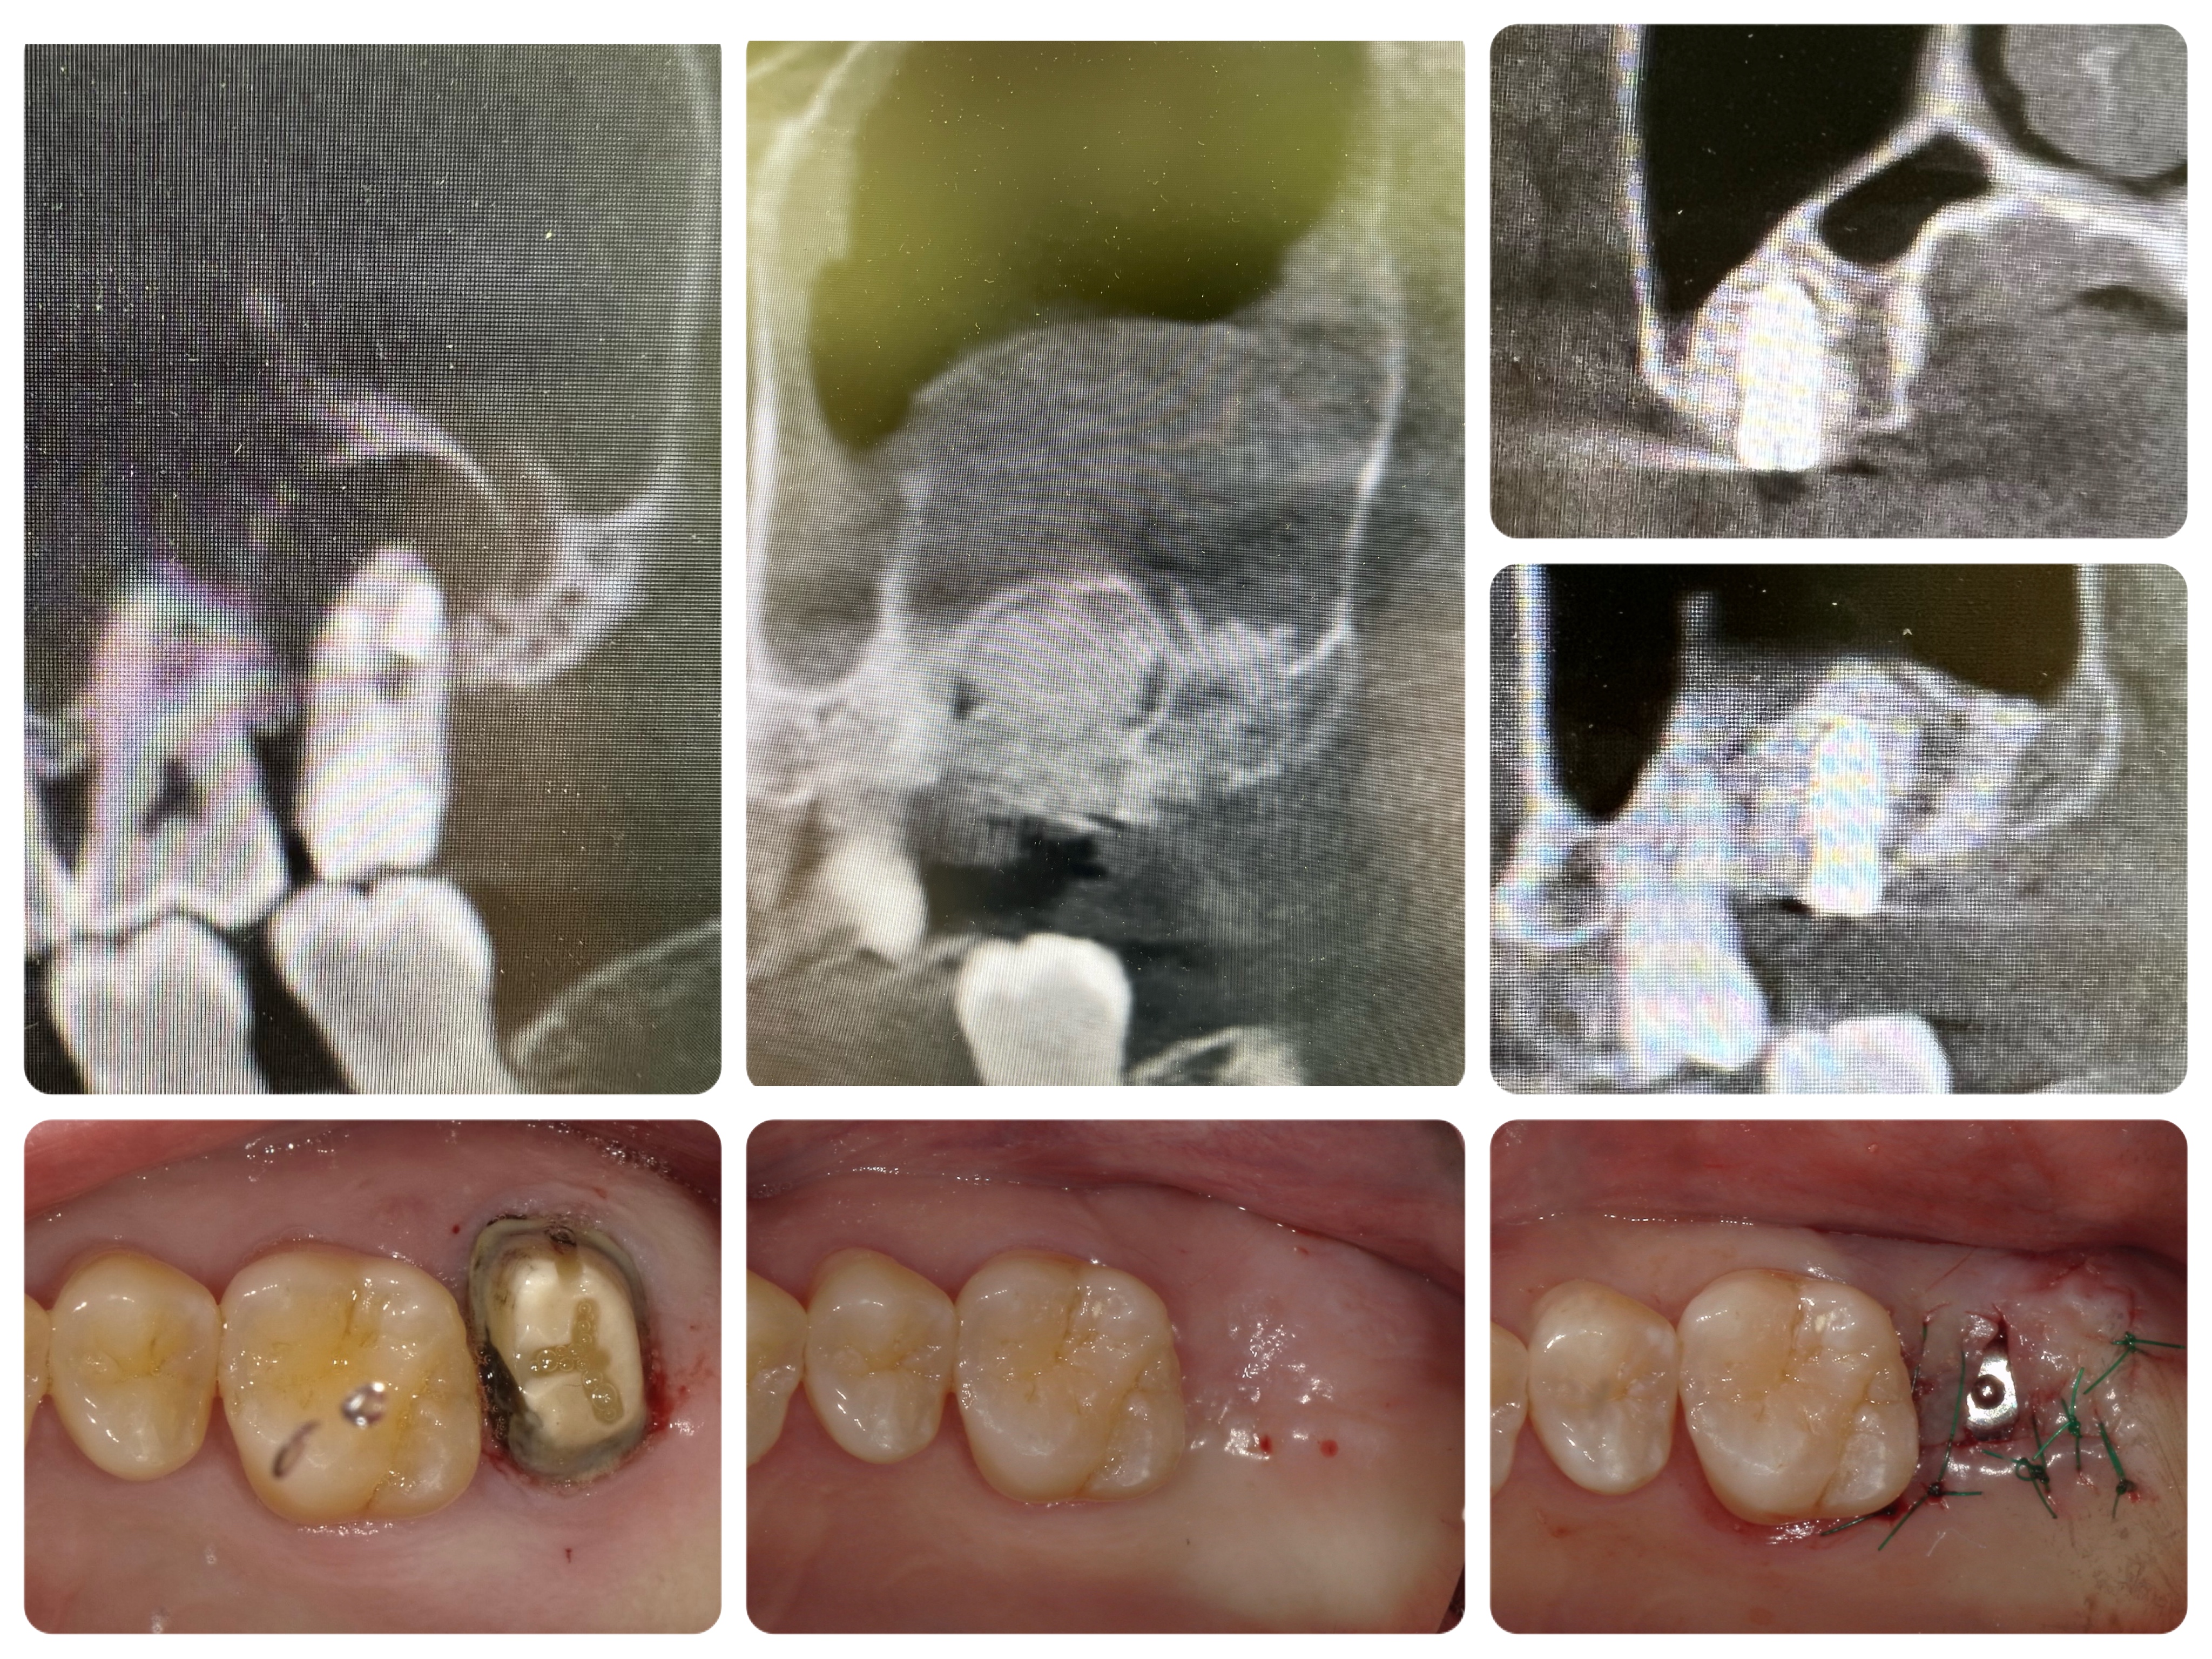

大きな根尖病巣があったので、ARP【歯槽堤保存術】後に一回法にてインプラント埋入!

歯肉厚みは2mm程度だったので骨縁下2mmに埋入。最近お気に入りのPositioning Burφ9.5mmで補綴主導でのフリーハンド埋入。φ4.0×7.0のMEGAGEN Implant AnyRidgeを使用。

上顎洞に触れる事もなく、フラップも極小で無事埋入できました。10週間後にScan予定です。お大事にしてください。